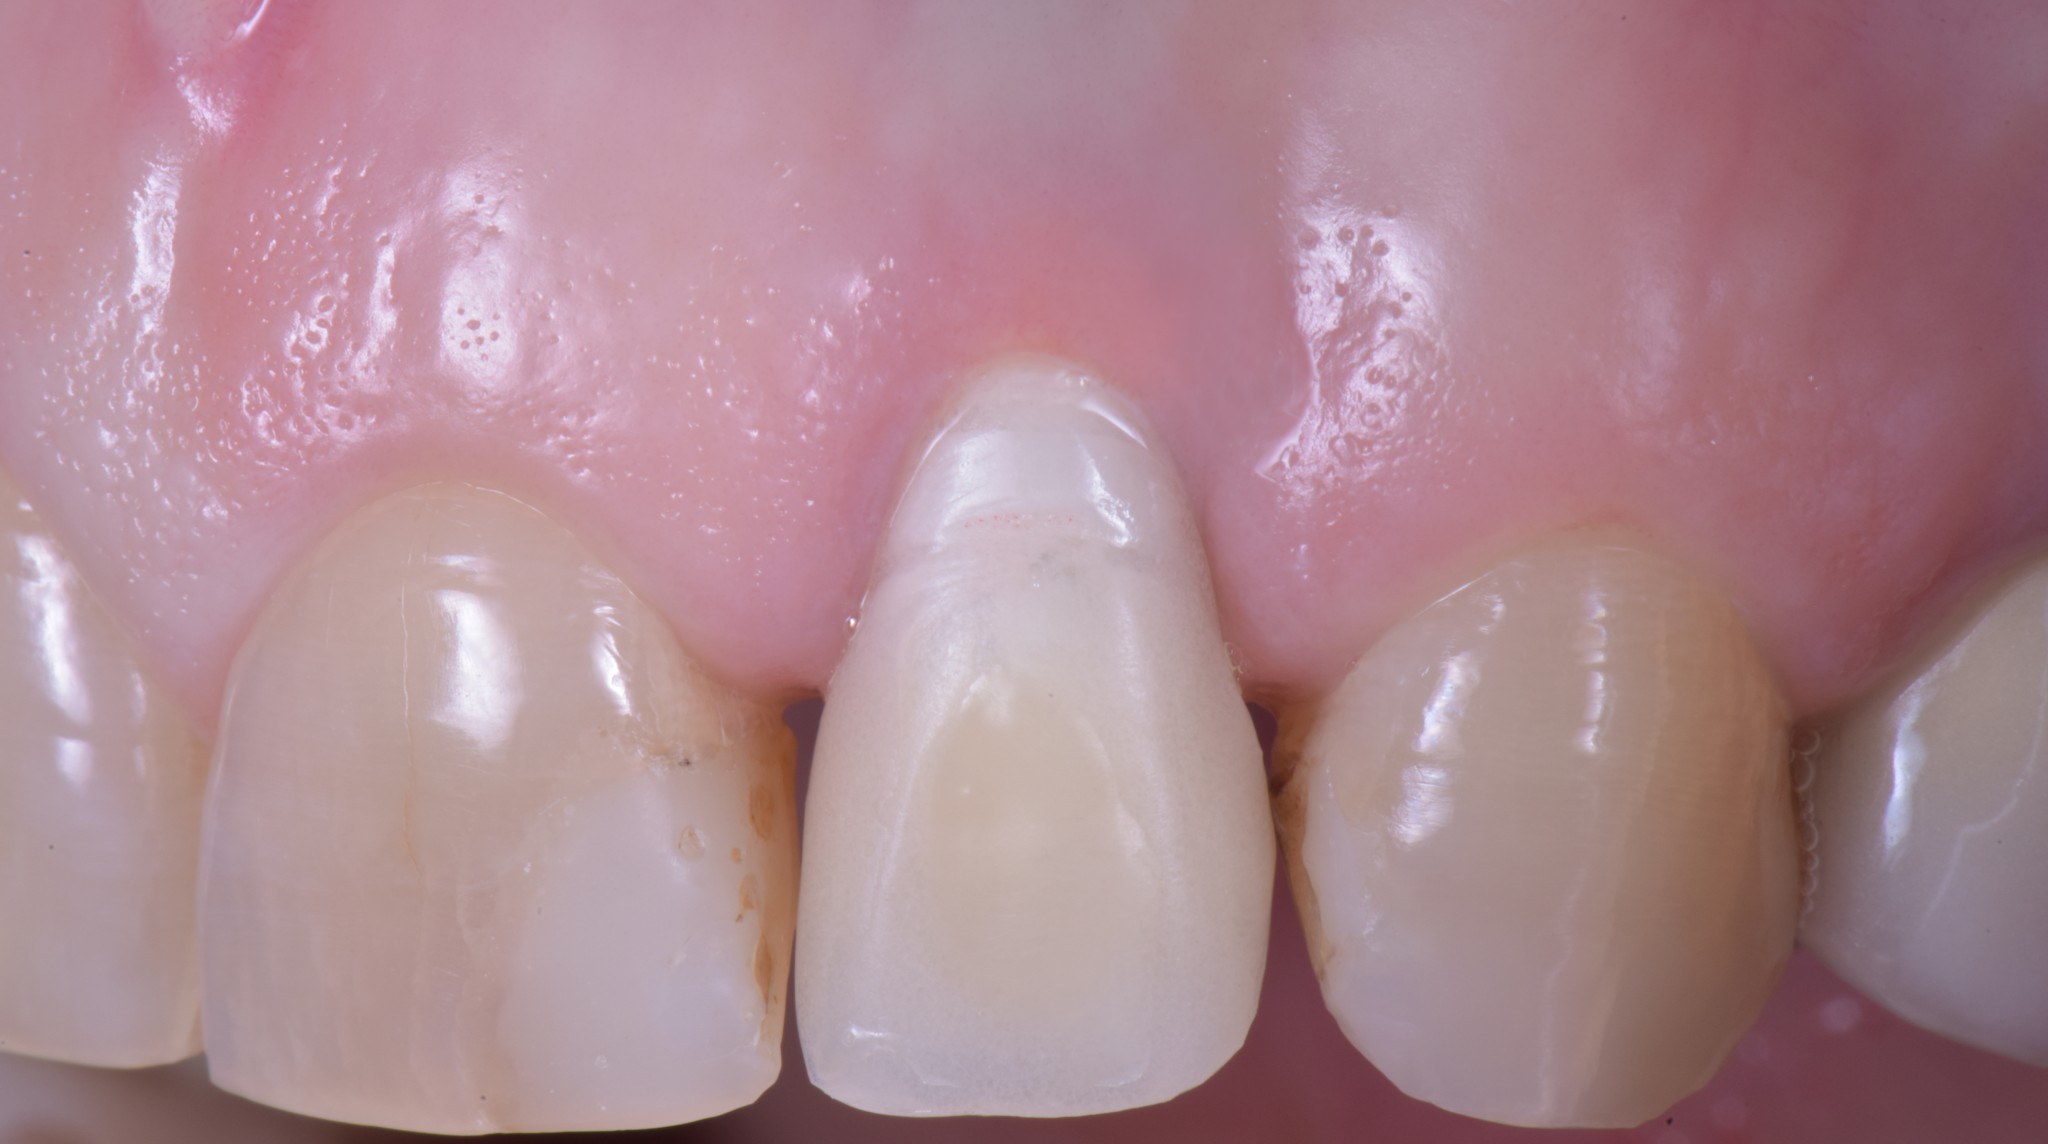

“Guarda questa lastra, cosa ne dici? Sta bene questo impianto?”

PERFETTO direi io, neanche un po’ di riassorbimento. Credo che tu sia d’accordo con me.

La signora Rosetta ha finito questo lavoro dal suo vecchio dentista esattamente 6 mesi fa. Appena messo la corona definitiva ha iniziato a lamentarsi di un fastidio continuo. Il collega, non so in base a quale presupposto teorico, ha rimosso il definitivo e rimesso il provvisorio.

Sintomo invariato, Rosetta continuava ad avere fastidio. Al che il collega, che non ho la più pallida idea di chi sia, ha attuato la TECNICA DELLE TECNICHE… che ho visto impiegare più volte e in molti studi nella mia giovanile carriera di marchettaro:

“Signora qui è tutto a posto, non so cosa dirle, lei non ha nulla”

- Fistola in sede vestibolare all’elemento 2.2 supportato da impianto

- Risultato estetico… (chiedo scusa ma qui devo tornare me stesso) di merda!

E non mi si venga a raccontare la storiella del “tu non puoi giudicare perché non sai quale fosse la complessità del caso” perché fino ad un anno fa in quella sede la paziente aveva il suo dente che è stato tolto e sostituito con un impianto perché si era decementata una vecchia corona e l’elemento era stato giudicato irrecuperabile da punto di vista conservativo. Quindi è stato fatto un impianto post-estrattivo di un dente con parodonto sano. Posso affermare con ottimo grado di certezza che le cose difficili sono altre!!

Ecco qua caro Lodovico, un impianto che mastica ottimamente, con una buona salute dell’osso di supporto (dopo ti spiego da cosa era causata la fistola), che riempie egregiamente il “buco” lasciato dall’estrazione ma con UNA GESTIONE DEI TESSUTI MOLLI DRAMMATICAMENTE PESSIMA!